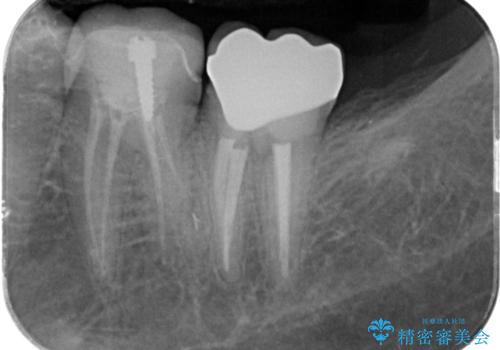

割れたクラウン 再発した虫歯の治療

虫歯をマイクロスコープを用いて丁寧に除去した後、ジルコニアセラミッククラウンによるクラウン製作を行います。

仕上がりの色調や自然さに満足いただくことができました。